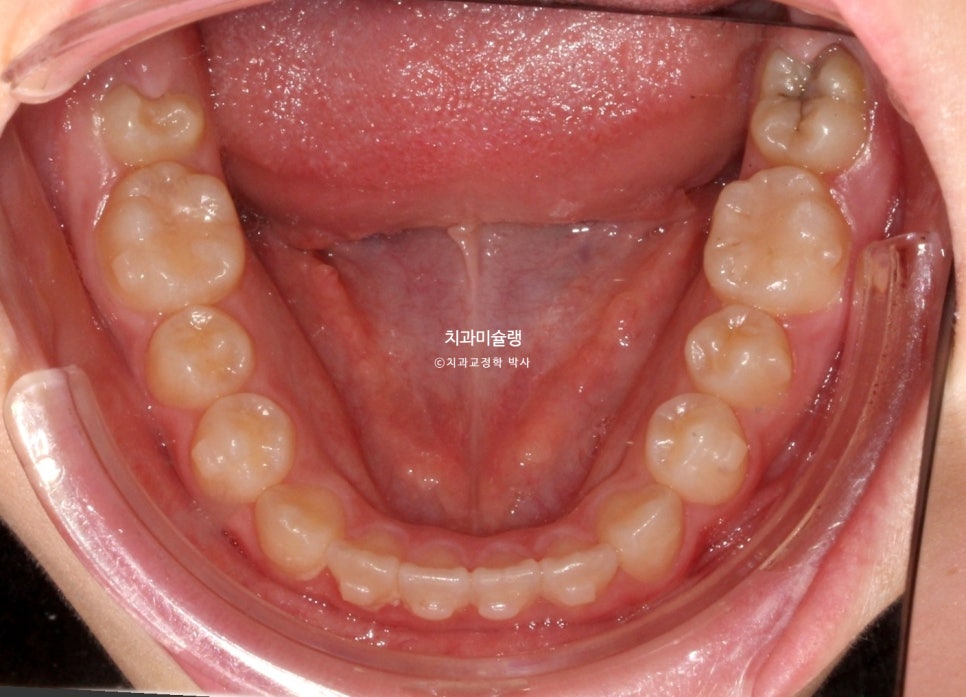

첫 번째 재제작 완료 후

11개 장치를 다 낀 후 모습입니다.

아래 앞니가 계획만큼 뒤로 들어가지 못해서 앞니가 여전히 먼저 닿습니다.

3급 교합관계가 여전히 남아있습니다.

두 번째 재제작 (17개 장치)

3급 교합관계 개선을 위해 두번째 재제작에 들어갑니다.